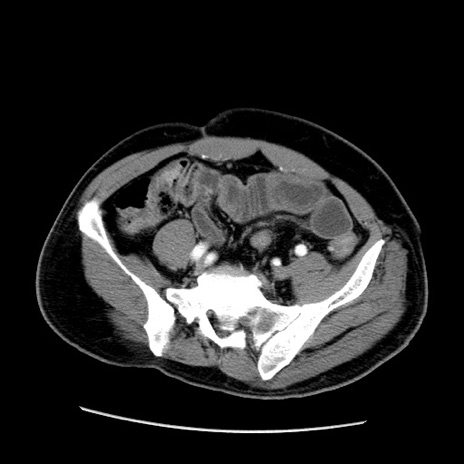

症例22(横断像)

【症例】50歳代男性

【主訴】腹痛

【現病歴】AVMからの被殻出血のため回復期リハ病棟入院中。 本日午後3時頃急に下腹部痛が出現した。

【既往歴】AVM、被殻出血、虫垂炎、高血圧

【身体所見】意識晴明、左半身不全麻痺、会話の理解は良好、36.5°C、腹部:膨隆、全体に板状硬、下腹部正中に圧痛点あり、反跳痛-、筋性防御不明、右下腹部にope scar

【データ】WBC 9400、CRP 0.06